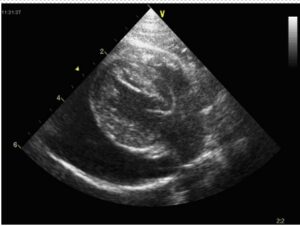

| Figure 4: Pericardial effusion in a cat. The nearly anechoic effusion is visible between the pericardium (visible as a white arcing line at the bottom of the view) and the bright epicardium that is seen on the surface of the myocardium. |